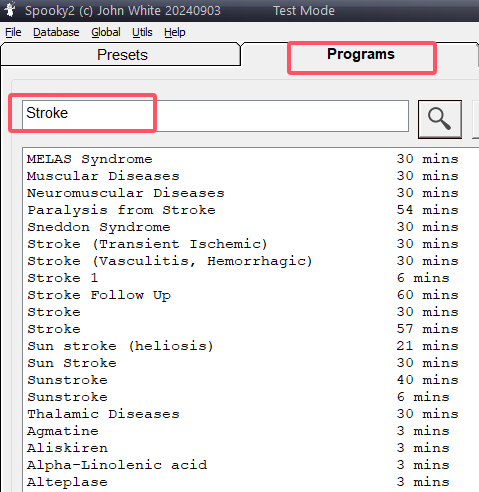

2: Zoek relevante programma’s

- Ga naar de Programs-tab en zoek op “Stroke” om programma’s te vinden die gericht zijn op specifieke symptomen zoals verlamming, spraakproblemen of slechte doorbloeding.